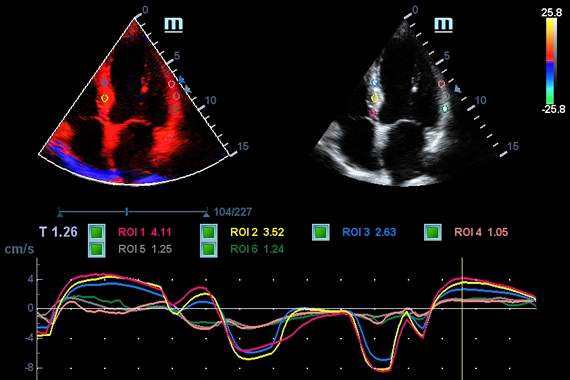

Клинические изображения

- TDI (Tissue Doppler imaging, including TDI Color, Power, PW and M mode) - пакет тканевой допплерографии, включая цветное картирование, импульсный тканевой допплер, энергетический тканевой допплер и тканевой М-режим

- TDI Quantification Analysis Software - количественный анализ тканевого допплера (необходима опция TDI)